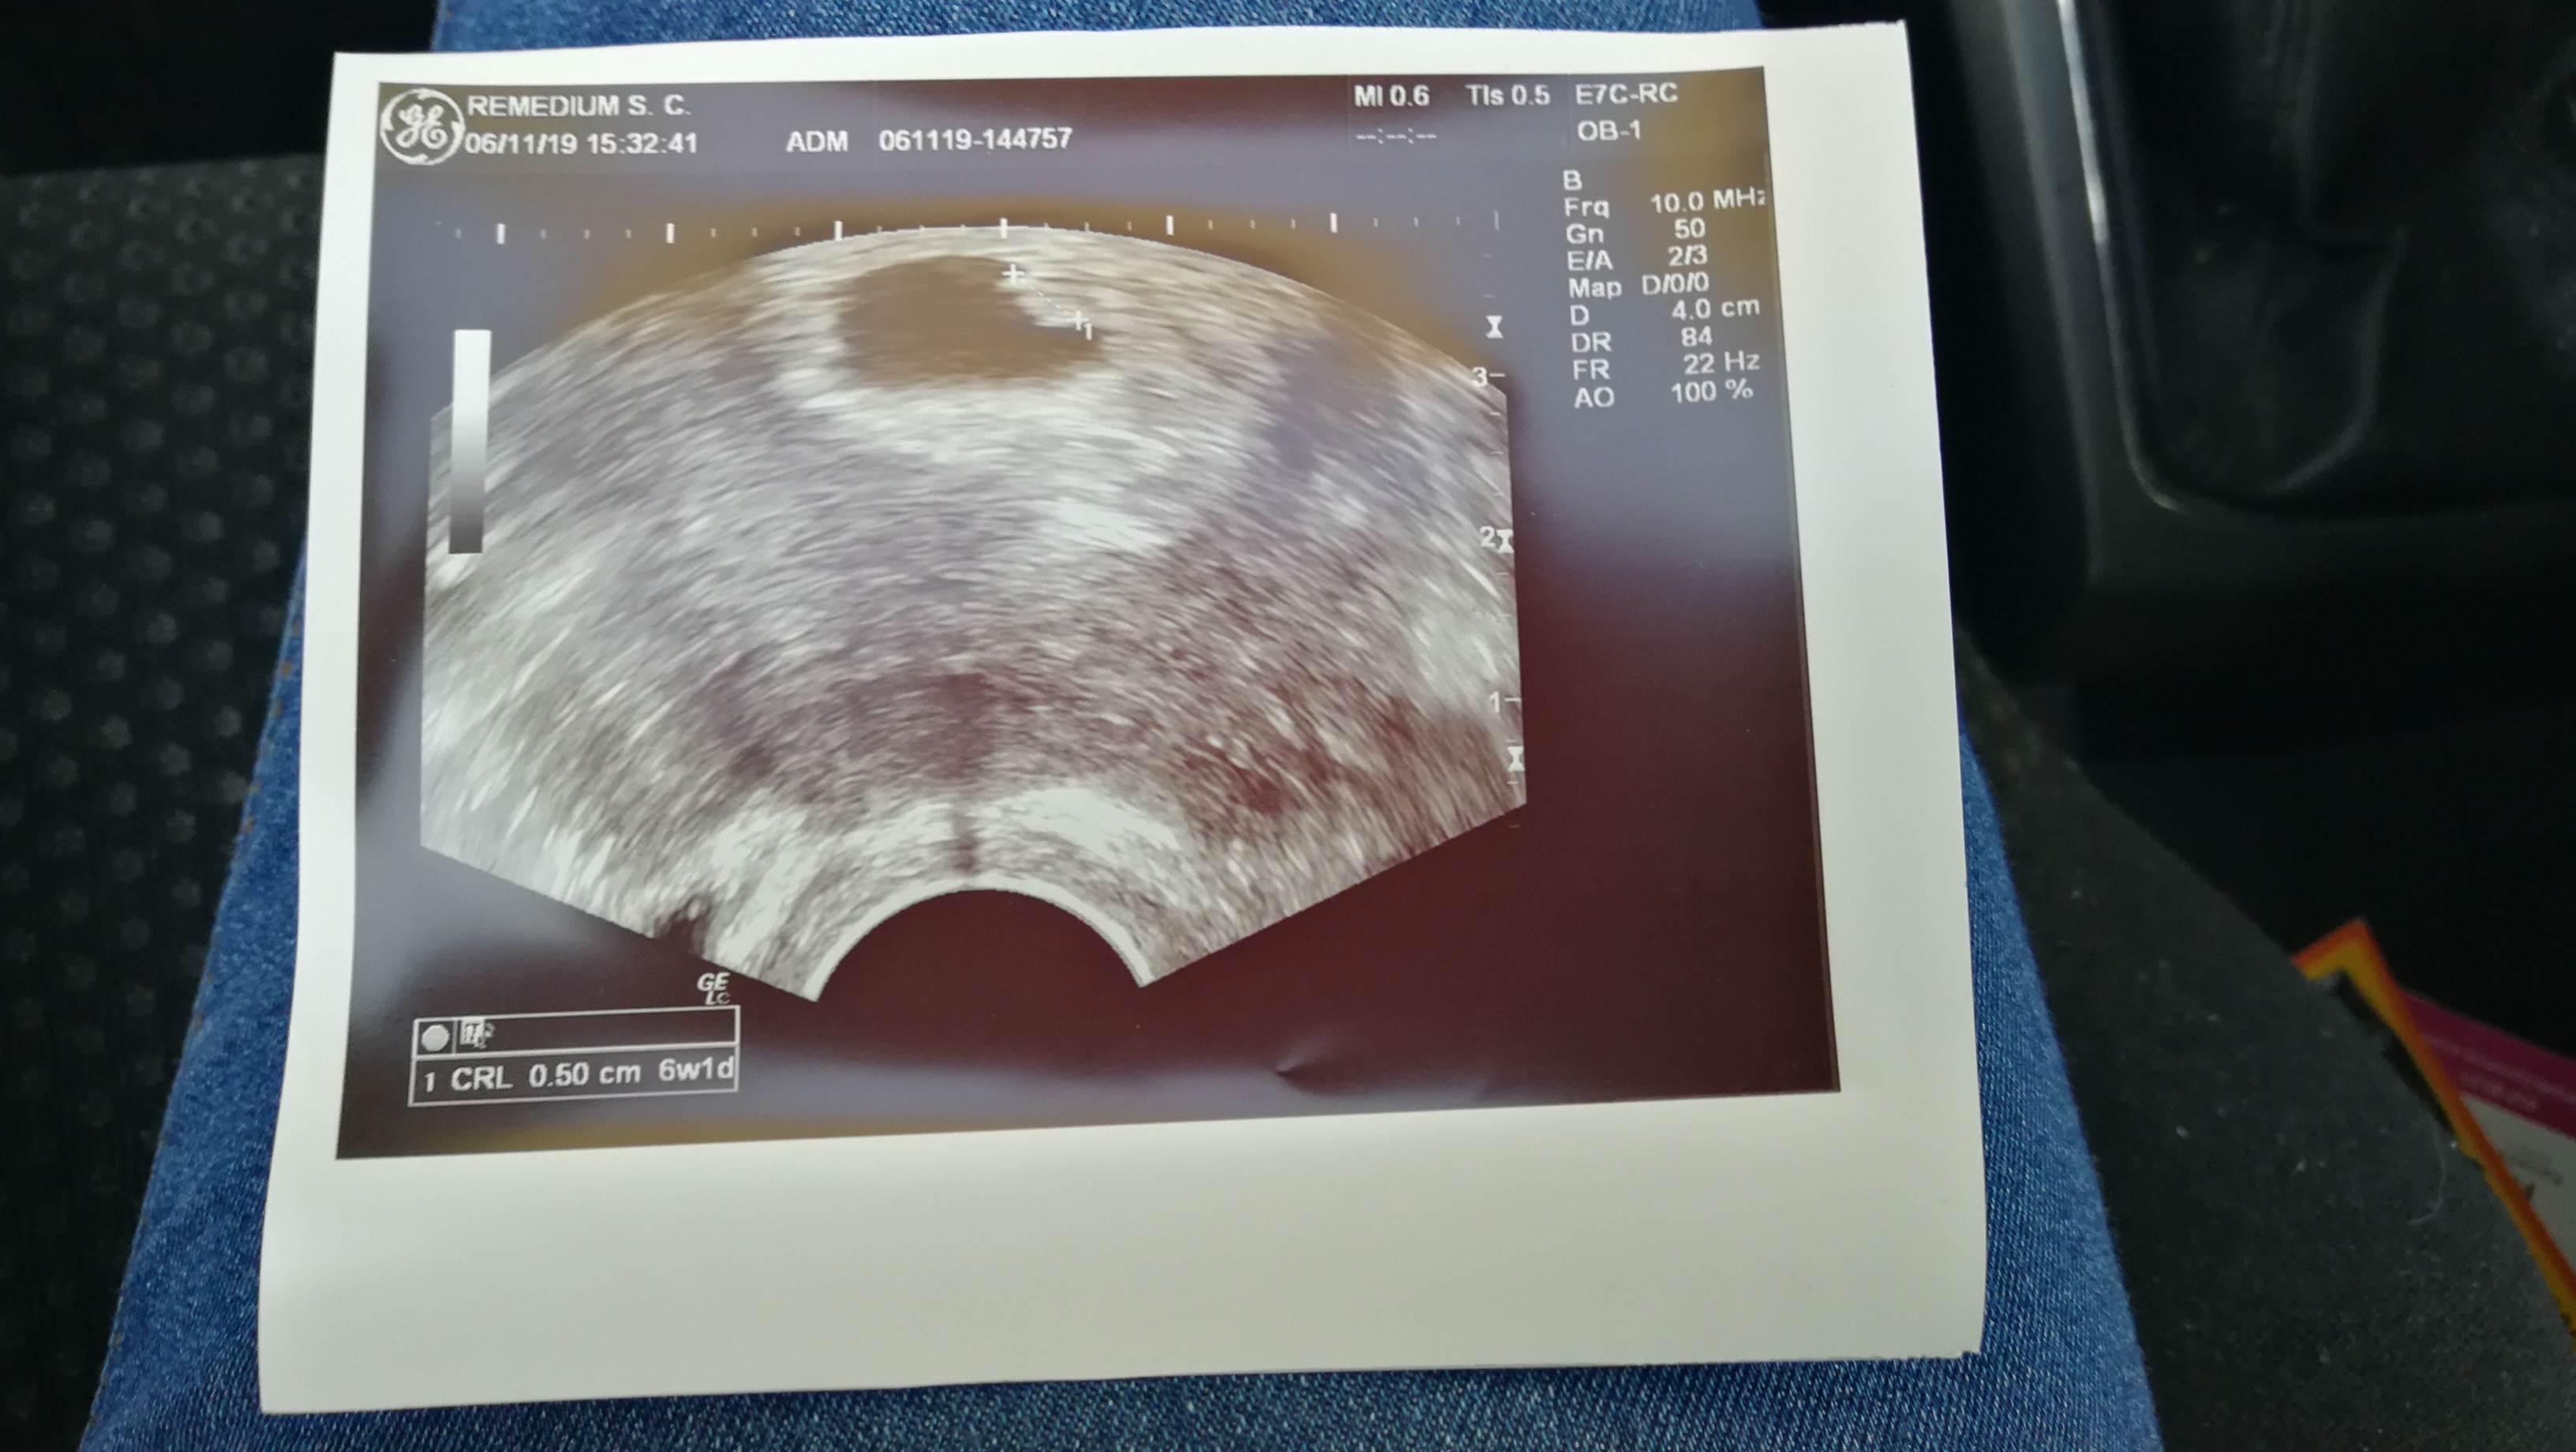

Po wizycie dziewczyny serduszko bije 6 tydzień i 1 dz jestem mega szczęśliwa, byle do konca bylo wszystko ok... Następną wizyta za 2 tyg. 25 listopada i chodze do lekarza na fundusz bo wcześniej chodzilam prywatnie i placilam duzo kasy a tak samo wszystko przebiega jak na fundusz to wole te pieniazki na witaminy wydac